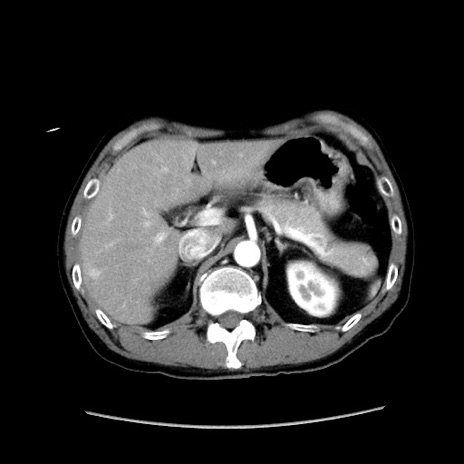

症例37(横断像)

【症例】40歳代 男性

【主訴】腹痛

【現病歴】4時間ほど前に電車に乗車中に臍部上より腹痛出現。徐々に増悪し起立困難となり、救急外来受診。生ものは数日食べていない。今朝お雑煮を食べた。

【身体所見】BT 36.8℃、BP 117/84mmHg、HR 91/min、SpO2 97%、苦悶様、腹部:臍上部広範囲圧痛あり、反跳痛±

【データ】WBC 8100、CRP 0.03